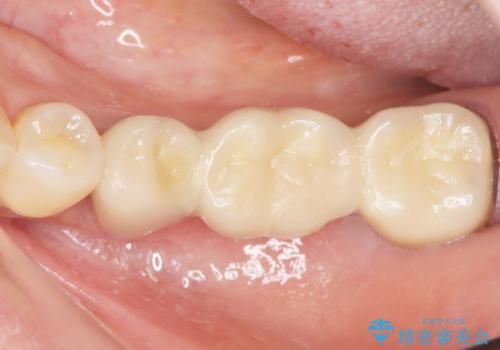

自然な仕上がりと咬み心地に喜んで頂けました。

クラウンの種類:メタルボンドクラウン エコノミー